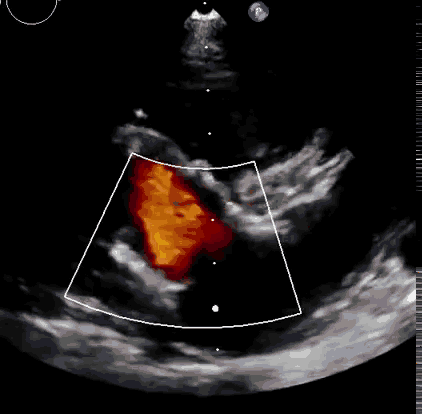

上海中山醫院葛均波院士、錢菊英院長、周達新教授、潘文志教授、潘翠珍教授、李偉教授共同完成此次臨床前研究。術后葛均波院士對Lux-Valve Plus的器械操作性能給予了高度評價,DSA和超聲影像也顯示出在本次研究中Lux-Valve Plus的安全性和有效性俱佳。

本次臨床前研究經右側頸靜脈置入LuX-Valve Plus輸送系統可調彎鞘管,在DSA及超聲引導下將人工三尖瓣瓣膜植入到原有三尖瓣位置,利用獨特的錨定技術將人工瓣膜支架可靠固定在預定的位置。